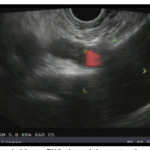

Frontiers in Endoscopy, Series #98

Endoscopic Ultrasound-Guided Therapy for Gastric Varices: Current Evidence and Emerging Perspectives

1. Introduction Gastric varices (GV) are a serious complication of portal hypertension, present in about 20% of cirrhotic patients compared to up to 85% with esophageal varices (EV).1,2 Though less […]